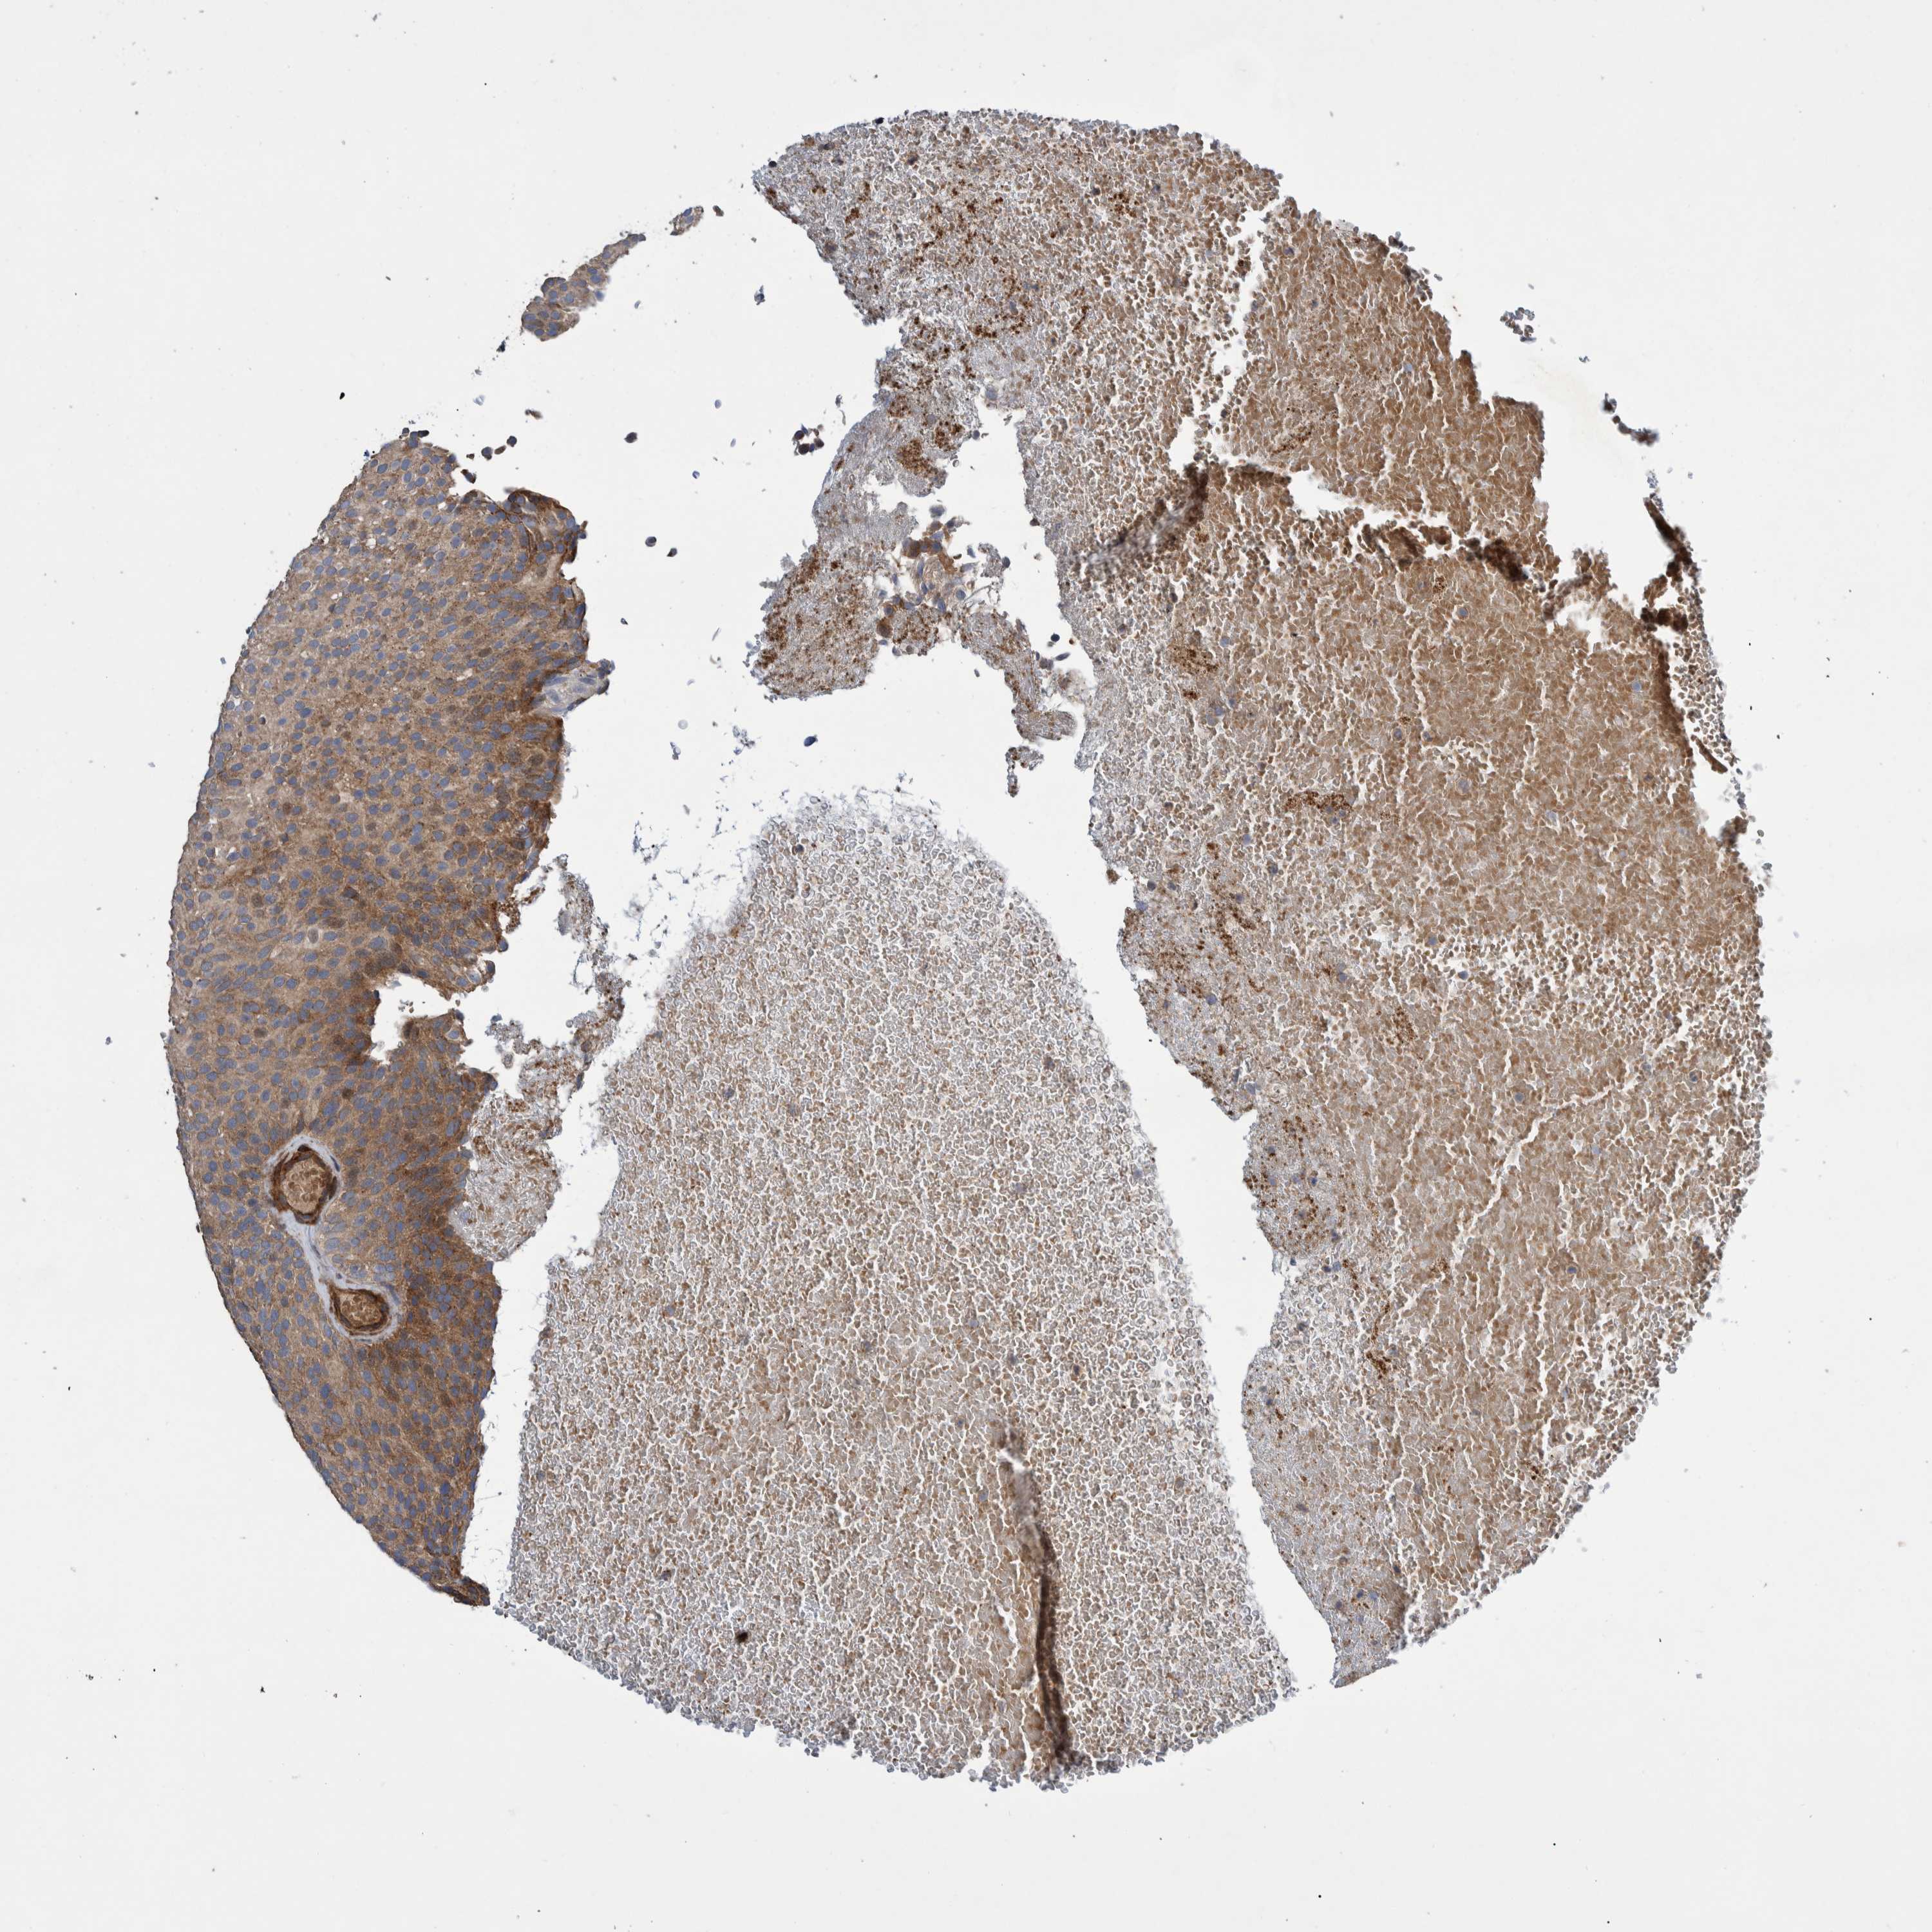

UROTHELIAL CANCER - Protein expressioni

A mouse-over function shows sample information and annotation data. Click on an image to view it in a full screen mode. Samples can be filtered based on level of antibody staining by selecting one or several of the following categories: high, medium, low and not detected. The assay and annotation is described here.

Note that samples used for immunohistochemistry by the Human Protein Atlas do not correspond to samples in the TCGA dataset.

Antibody stainingi

Antibody staining in the annotated cell types in the current human tissue is reported as not detected, low, medium, or high, based on conventional immunohistochemistry profiling in selected tissues. This score is based on the combination of the staining intensity and fraction of stained cells.

Each image is clickable and will lead to virtual microscopy that enables deeper exploration of all samples and also displays staining intensity scores, fraction scores and subcellular localization as well as patient and tissue information for each sample.

Antibody HPA018173

Antibody HPA023211

Staining

High

Medium

Low

Not detected

Intensity

Strong

Moderate

Weak

Negative

Quantity

>75%

75%-25%

<25%

None

Location

Nuclear

Cytoplasmic/membranous

Cytoplasmic/membranous,nuclear

Urothelial carcinoma, Low grade

Urothelial carcinoma, High grade